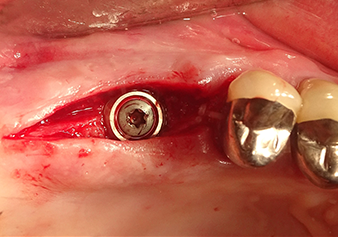

Implant bed preparation and augmentation

Following an intermediate check (Fig. 4) a further preparation step was performed (Fig. 5). Afterwards, the hydraulic Z35P instrument was used to lift the membrane to the desired position (Fig. 6 and 7). This was followed by further piezosurgical preparation of the implant bed, concluded with a rotary bur and shoulder milling cutter up to the implant diameter of 4.8 mm. Before the implant was inserted, the augmentation material (particle size approx. 0.8-1.6 mm) was introduced underneath the Schneiderian membrane (Fig. 8).

Implantation and prosthetic restoration

To move the augmentation material in the direction of the maxillary sinus atraumatically, the implant was inserted very slowly by hand (Fig. 9). In the process, the membrane was pushed in the cranial direction once again. After two months, the surgical site healed without irritation. Six months later, the x-ray check showed a significant increase in opacity as an indication of ossification (Fig. 10). The prosthetic restoration was carried out with a metal-ceramic crown.